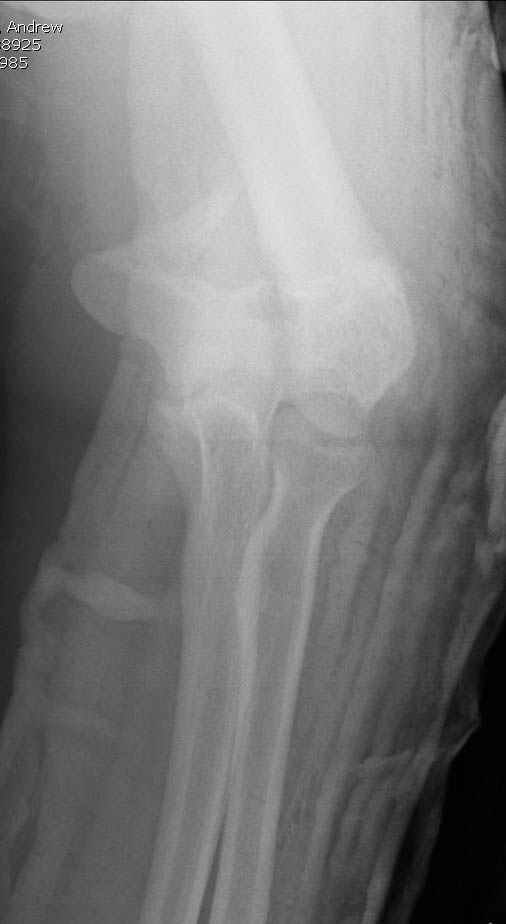

Примерный случай, только перелом был открытый, в задне-медиальной стороне рана около 2 см по характеру "изнутри кнаружи", неврологический статус со слабостью сгибания мизинца, также слабая абдукция и аддукция указательного пальца и сгибания в кисти.

Этапы операции на снимках....